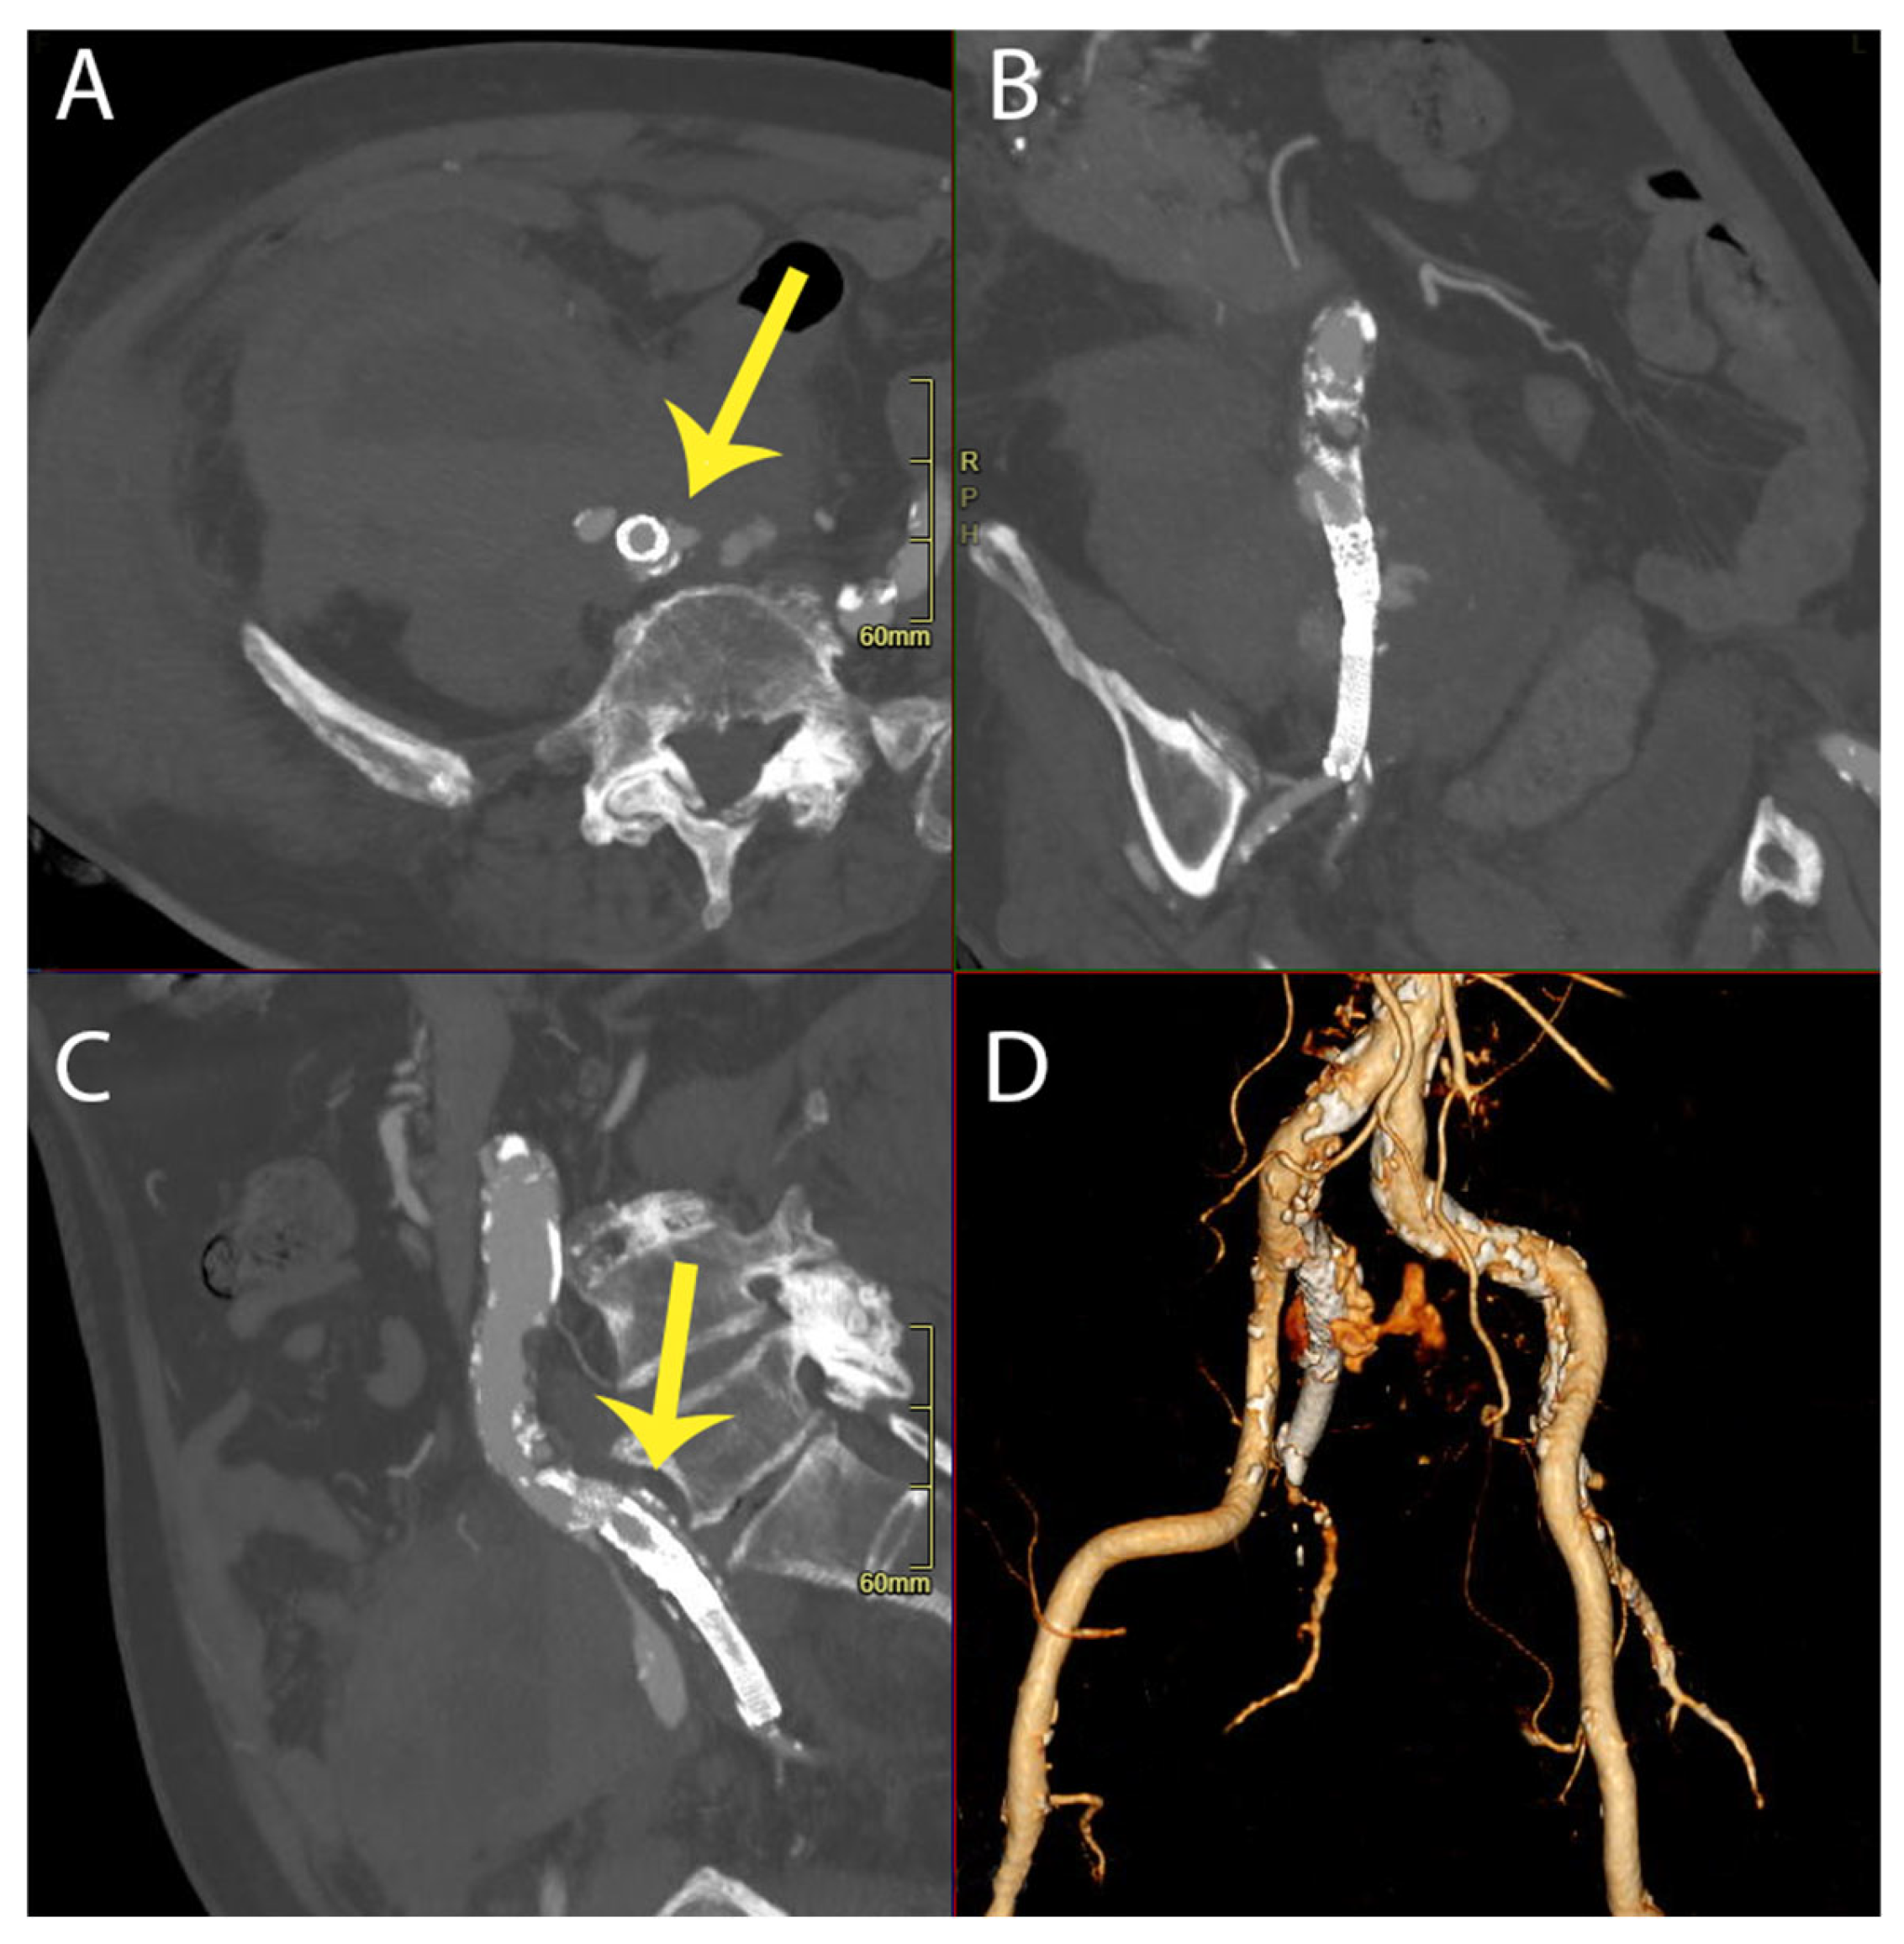

An intravenous contrast-enhanced abdominal CT scan demonstrated an “aneurysmatic dilatation of the right iliac bifurcation”, predominantly affecting the IIA, with a diameter of 4 cm and evidence of extraluminal extravasation of the contrast media, indicative of a rupture. Additionally, blood effusion was noted in the perianeurysmal space, perihepatic area, right paracolic gutter, and pelvic cavity. The patient was promptly taken to the operating theatre, where permissive hypotension and hypovolemia were employed. See Figure 1.

Figure 1. Multiplanar reformation (MPR view in axial (A), coronal (B), sagittal (C)) and 3D reconstruction (D) of preoperative CT angiography, showing right internal iliac artery rupture (highlighted with arrows).